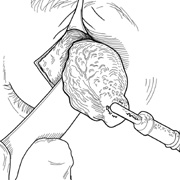

A variety of specialized orbital instruments, including retractors, dissectors, and bone-cutting tools, are available. Standard orbital retractors include several sizes of Sewall and malleable ribbon retractors. Retractors are useful in dissecting through the orbital fat; in addition, they offer exposure once the mass is identified. Placement of neurosurgical cottonoids beneath the retractor helps to keep orbital fat from prolapsing into the wound. Several types of periosteal elevators are useful; the most common is a Freer periosteal elevator. Numerous air-driven bone saws and drills are available. Bone rongeurs of several sizes should be on the surgical instrument tray. One of the various orbital miniplating or microplating systems may be useful for reattaching bone flaps and reconstructing bony defects. A retinal or glaucoma cryoprobe is helpful for applying traction to encapsulated solid or cystic orbital masses to facilitate their dissection from surrounding orbital tissues. For combined sinus and orbital surgery, the use of a nasal endoscope sometimes is helpful. Techniques involving many of these instruments frequently are not emphasized in ophthalmic residency training. Familiarity in these instruments must be obtained before beginning orbital surgery.